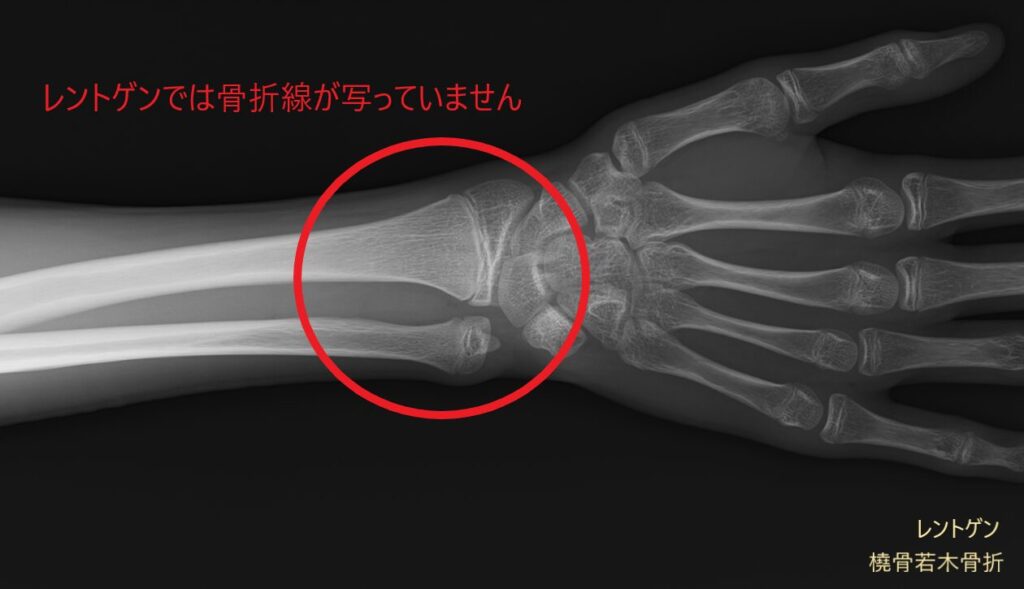

レントゲン画像には映りにくい筋肉や腱、靭帯などの状態に加え、骨の様子もあわせて確認できます。